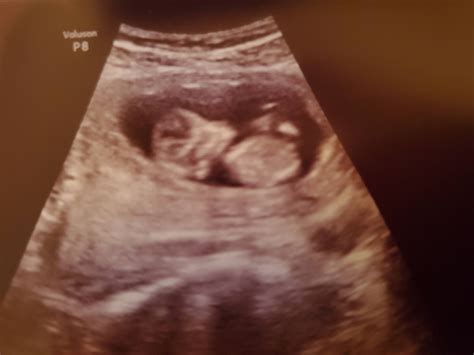

The 12 week ultrasound is usually performed transabdominally, meaning the ultrasound probe is moved over the abdomen. In some cases, a transvaginal ultrasound may be used for better visualization, especially if the baby is positioned deeply in the pelvis.

During the procedure, the technician will apply a gel to the abdomen to enhance the transmission of sound waves. The probe will then be moved over the abdomen to capture images of the fetus. The entire process typically takes about 20-30 minutes.

During the 12 week ultrasound, several key measurements and assessments are made:

• Crown-Rump Length (CRL): This measurement from the top of the baby’s head to the bottom of the spine helps determine the gestational age and due date.

• Nuchal Translucency (NT): The thickness of the fluid-filled space at the back of the baby’s neck is measured. This measurement, along with maternal age and blood tests, helps screen for chromosomal abnormalities.

• Heartbeat: The baby’s heartbeat is checked to ensure it is within the normal range.

• Anatomy: The technician will look for the presence of the nasal bone, which is an important marker for Down syndrome. They will also check for the presence of both arms, legs, and the stomach bubble.